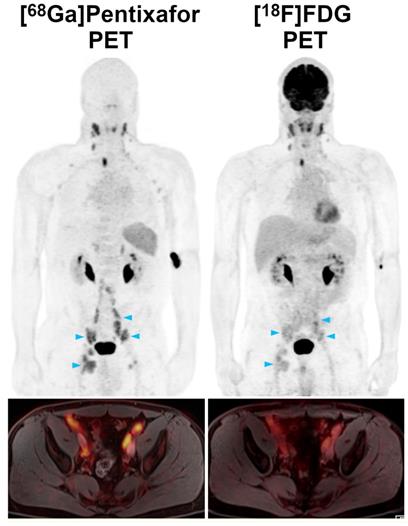

In the 19 patients who underwent PET/MRI with both tracers, per region agreement between [68Ga]Pentixafor-PET (positive in 114 regions) and [18F]FDG-PET (positive in 85 regions) was 74.6%, excluding the bone marrow and spleen. Of the 85 [18F]FDG-PET positive regions, six (7.1%) showed uptake not higher than the liver background in 4/19 (21.1%) patients. Compared to the reference standard, [68Ga]Pentixafor-PET showed a significantly higher sensitivity (100.0%; CI, 100.0-100%) than [18F]FDG-PET (75.2%; CI, 66.3-82.3%) (P<0.001) (Figures 1 and 2). With seven false-positive regions, PPV was slightly, but not significantly (P=0.21), lower for [68Ga]Pentixafor-PET (94.0%; CI, 87.9-97.1%) than for [18F]FDG-PET (96.5%; CI, 89.6-98.9%), which was false-positive in only two regions.

Figure 1

Pre-therapeutic [68Ga]Pentixafor-PET/MRI and [18F]FDG-PET/MRI of an 82-year-old female MCL patient. [68Ga]Pentixafor-PET detects considerably more nodal lymphoma manifestations than [18F]FDG-PET, and stronger tracer uptake in several lesions/regions. All lymph nodes with focal increased [68Ga]Pentixafor uptake corresponded to clearly enlarged lymph nodes on diffusion-weighted MRI (DWI). Representative examples of such [68Ga]Pentixafor-PET-positive lesions with no or low [18F]FDG uptake, but obvious lymphadenopathy on DWI, are marked by blue arrowheads (left axially, retroperitoneal/periaortic, and right pelvic regions).

Pre-therapeutic [68Ga]Pentixafor-PET/MRI and [18F]FDG-PET/MRI of a 52-year-old male MCL patient. Several infradiaphragmatic nodal lymphoma manifestations (blue arrowheads) that show strong [68Ga]Pentixafor uptake on PET (top) and fused color-coded PET/MRI (bottom) show only moderate-to-low [18F]FDG uptake that does not, or only slightly, exceed the [18F]FDG uptake of the liver. Consequently, measured tumor-to-background ratios (TBRblood, TBRliver) are higher for [68Ga]Pentixafor-PET than for [18F]FDG-PET.